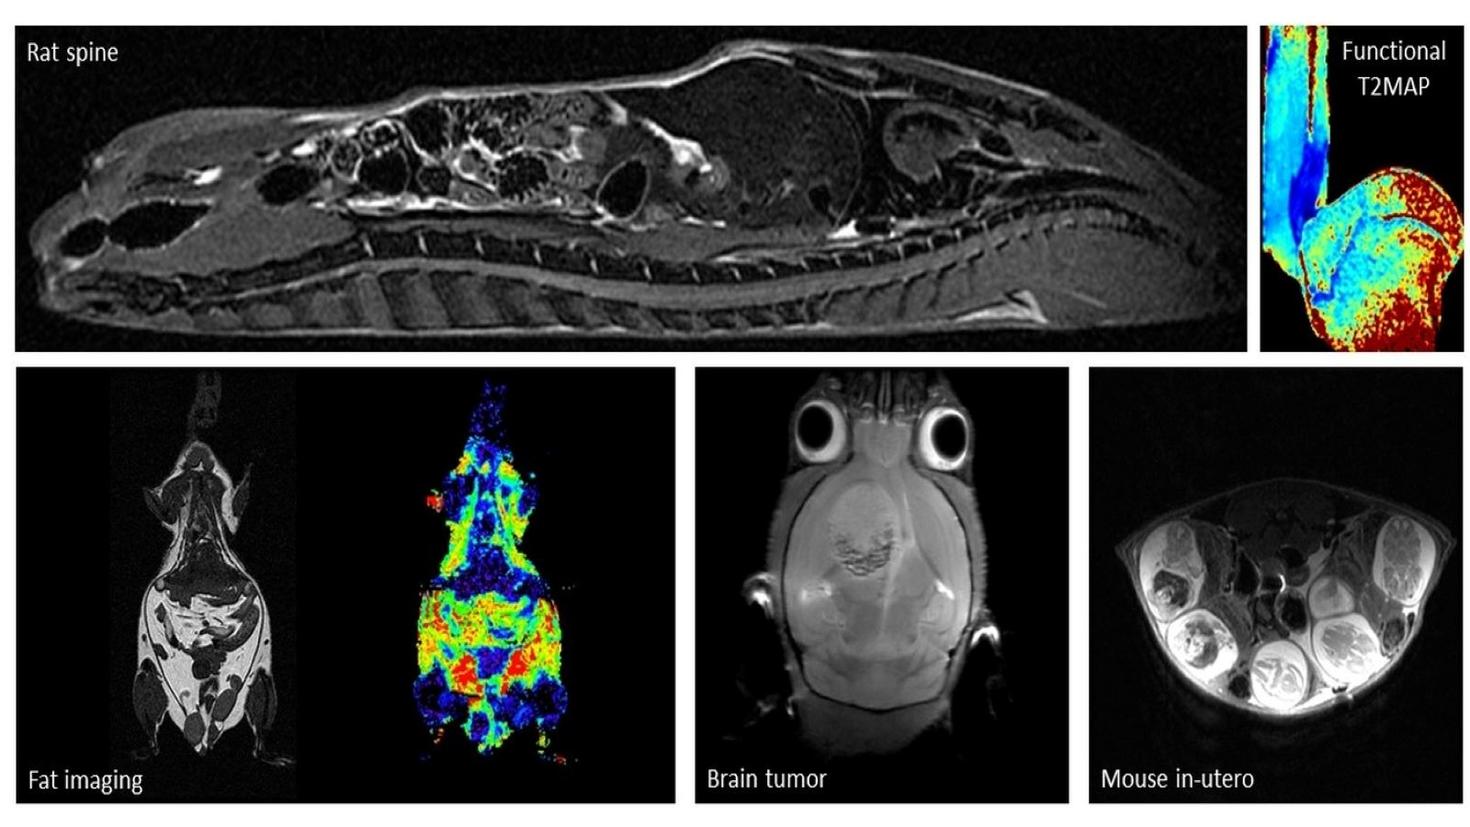

Exemples d'images acquises par notre IRM 7T

IRM d'une colonne vertebrale d'un rat